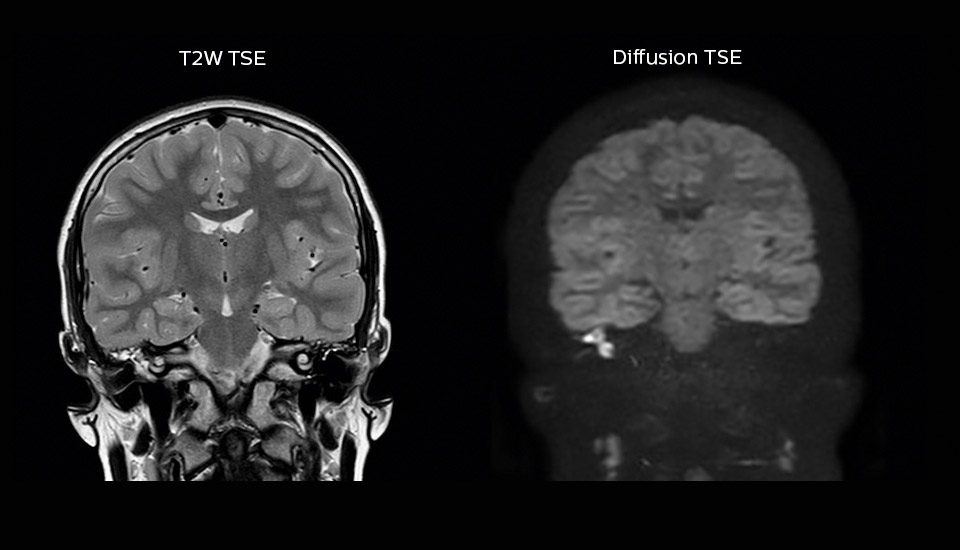

Since the installation of Ingenia 1.5T in the new building of Meander Medical Center, the MRI team has enjoyed many successes in improving their MRI scanning by implementing the latest techniques available to them, such as Diffusion TSE for distortion-free images, mDIXON TSE for adding fat-free imaging without adding time, and motion correction with MultiVane XD.

“Imaging cholesteatoma, benign tumors of the middle ear, has been a huge challenge,” says Dr. Heggelman. “We used to do CT, but then we were unsure if we were looking at an inflammation or a cholesteatoma. Also determining if residual cholesteatoma exist after surgery or visualizing recurrence used to be very difficult. Adding Diffusion TSE in our MRI protocol now effectively addresses this.” “Diffusion TSE is far less sensitive to susceptibility differences than previously used EPI sequences. We appreciate the high resolution and the robustness of the sequence. The quality is so good that our confidence has increased. Also our ENT (ear, nose, throat) physicians are excited about the high resolution, the excellent lesion delineation and the sensitivity and specificity.”